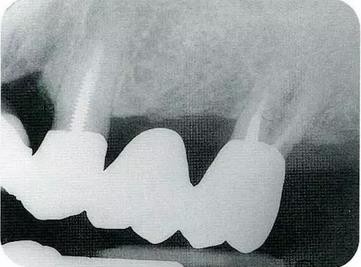

▼圖16-1 ▼圖16-2

圖16-1 對(duì)右上6.7分叉部病變處理時(shí),對(duì)包括右上4.5進(jìn)行齦瓣分割,確認(rèn)骨缺失狀態(tài)。右上7頰側(cè)存在著12mm的骨緣下缺失。

圖16-2 右上6水平的分叉部病變到達(dá)了III度。